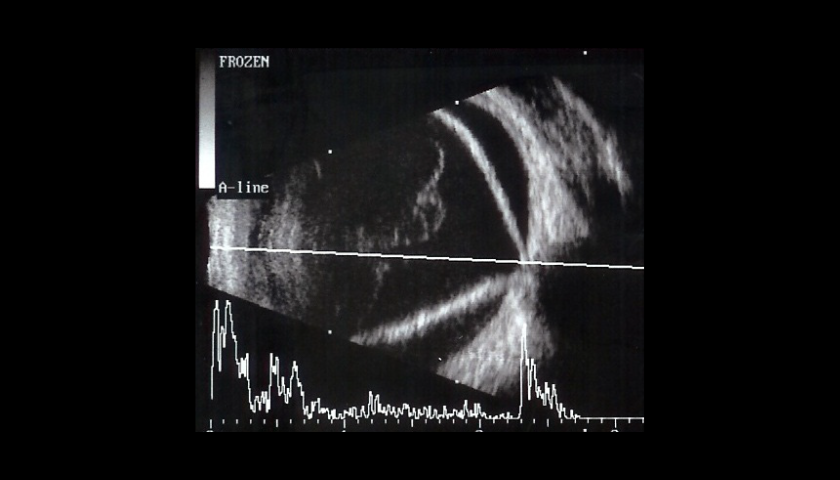

O tratamento das Membranas Epirretinianas é cirúrgico. Para a extração da Membrana Epirretiniana é necessária a realização de uma Vitrectomia via pars plana.

Nem todas as Membranas Epirretinianas requerem tratamento. Se a condição for muito leve, e tiver pouco ou nenhum efeito na visão, o tratamento será geralmente desnecessário estando indicado o acompanhamento clínico e pela avaliação do OCT.

Em casos mais graves, a cirurgia da Membrana Epirretiniana é necessária para remover a Membrana.